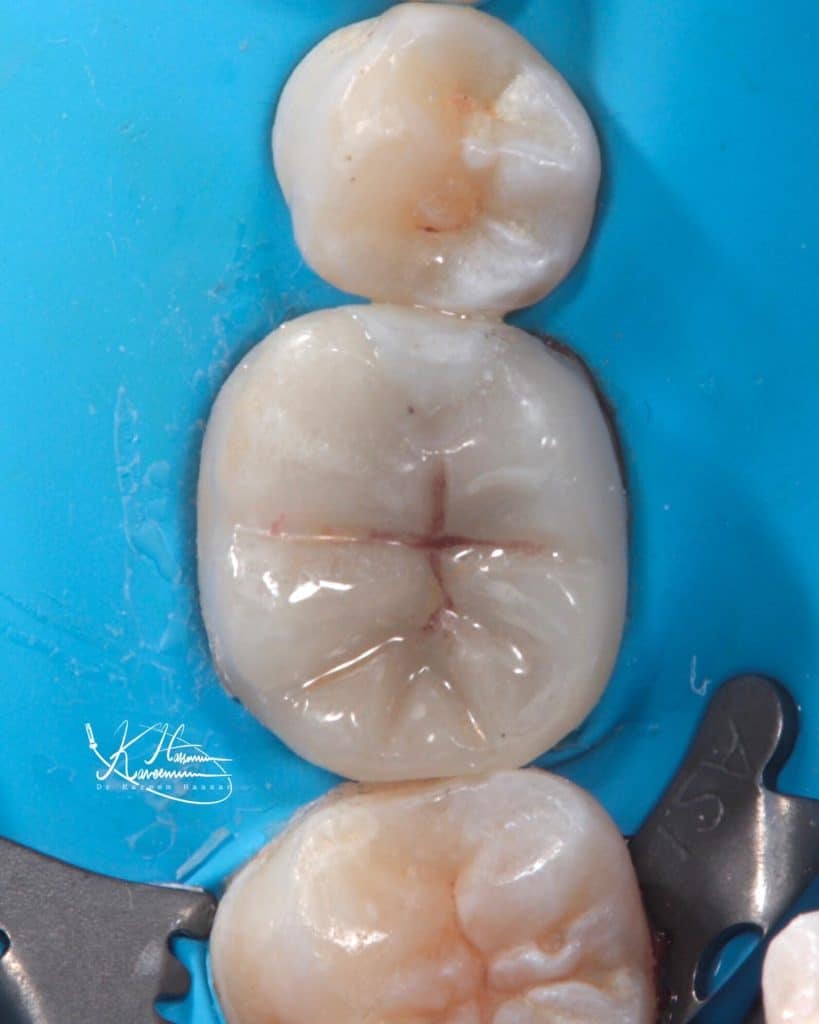

In this case we preserved the vitality of pulp

– IDS with Clearfil SE bond followed by Majesty flow as RC

-ribbond

-EMAX bonded with heated AP-X

Final result